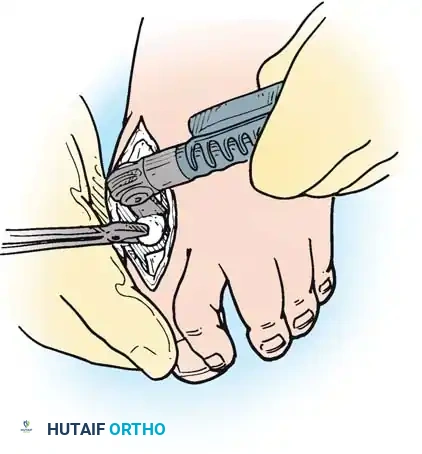

- Resection: The extensor tendons are retracted or lengthened (Z-plasty). The dorsal capsule is opened, and the collateral ligaments are sharply divided to allow plantarflexion of the metatarsal.

- Osteotomy: An oscillating saw is used to resect the metatarsal heads at the anatomical neck. It is imperative to create a smooth, parabolic cascade (the 2nd metatarsal should be the longest, tapering down to the 5th).

- Soft Tissue Balancing: The plantar plate and fat pad, which have migrated distally, are mobilized and pulled proximally under the remaining metatarsal stumps. If the toes remain contracted, closed osteoclasis or PIP joint resection arthroplasties may be performed.

- Pinning: Smooth Kirschner wires (K-wires) are driven antegrade through the toes and retrograde into the metatarsal shafts to hold the toes in neutral alignment.

Intraoperative view demonstrating the exposure and resection of the lesser metatarsal heads to decompress the forefoot and allow reduction of the dislocated digits.